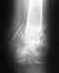

Оскольчатые переломы верхней и нижней ветвей лонной кости слева, перелом боковых масс крестца с обеих сторон, перелом S2 позвонка.

Добрый день, уважаемые доктора. Ситуация такая: женщина 78 лет упала в душе месяц назад. На следующий день поехали в травмапункт, там сделали рентген, сказали - переломов нет, ушибы, мажьте мазью, все пройдет. Ничего не проходило, только становилось хуже. Сначала болело только с левой стороны, потом болеть стала правая нога. Сидеть и ходить очень больно. Сами сделали МРТ и КТ. В результате обнаружили перелом костей таза в 5 местах: Оскольчатый перелом верхней лонной кости (в области лонного сочленения) с расхождением костных фрагментов до 8 мм. Перелом нижней ветви лонной кости слева в дистальном отделе, перелом боковых масс крестца с обеих сторон, перелом S2 позвонка. Положили в больницу (г. Москва) в отделение травматологии 22 февраля вечером, в выходные врачей не было, а в понедельник 26 февраля врач сказал - выписываем. Операция нецелесообразна. Дома все срастется. Ходите с ходунками. Вопрос - действительно ли нет необходимости в операционном вмешательстве или каким-либо другим способом собрать и зафиксировать обломки? Есть ли признаки срастания костей? Можно ли ходить? Сидеть? Есть ли реабилитационный центр в Москве для восстановительного лечения после таких травм?